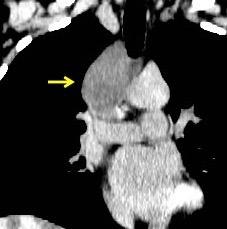

“Draped aorta”.

Indica rotura aórtica reciente. Se manifiesta por una pared aórtica posterior o el contacto con el borde lateral vertebral borrados por la hemorragia.

A. Yudin, Metaphorical

Rotura aneurisma de Aorta descendente.

Dolor. (10 días antes: "Rotura inminente”)